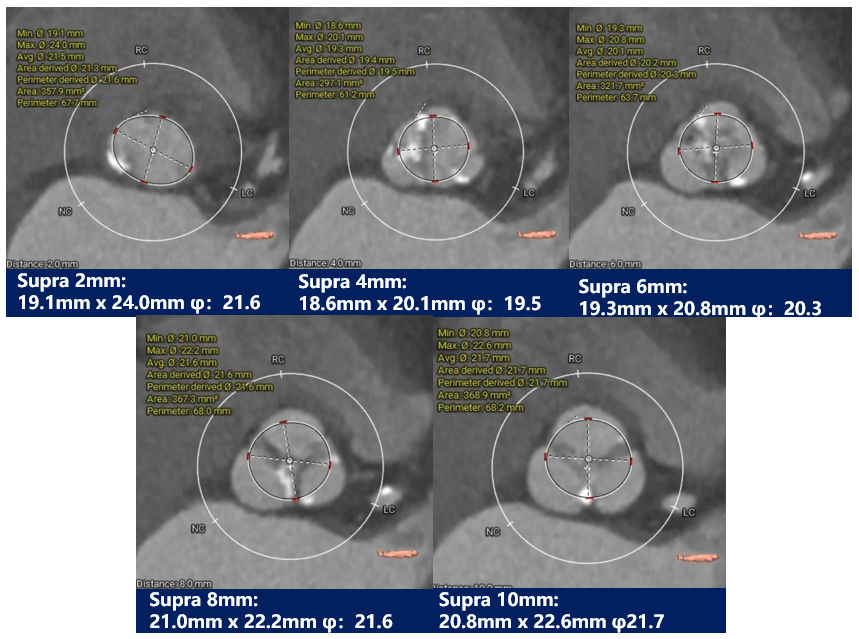

主动脉根部评估:

三叶式主动脉瓣,中度钙化并瓣叶增生肥厚,钙化分布欠均匀,主要分布在瓣叶边缘及血管壁附着缘-左右冠高度可,冠脉切线位瓣叶长度<冠脉开口到瓣叶根部附着缘距离;冠脉可见散在钙化-流入端呈收口,瓦氏窦、STJ及升主动脉内径偏小。

瓣上测量:

中度钙化三叶式主动脉瓣,存在假体瓣膜形变、瓣环撕裂及根部损伤风险,人工瓣膜锚定力尚可,有瓣膜移位风险,有少量瓣周漏可能。